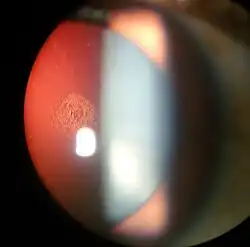

| Magnified view of a cataract seen on examination with a slit lamp | |